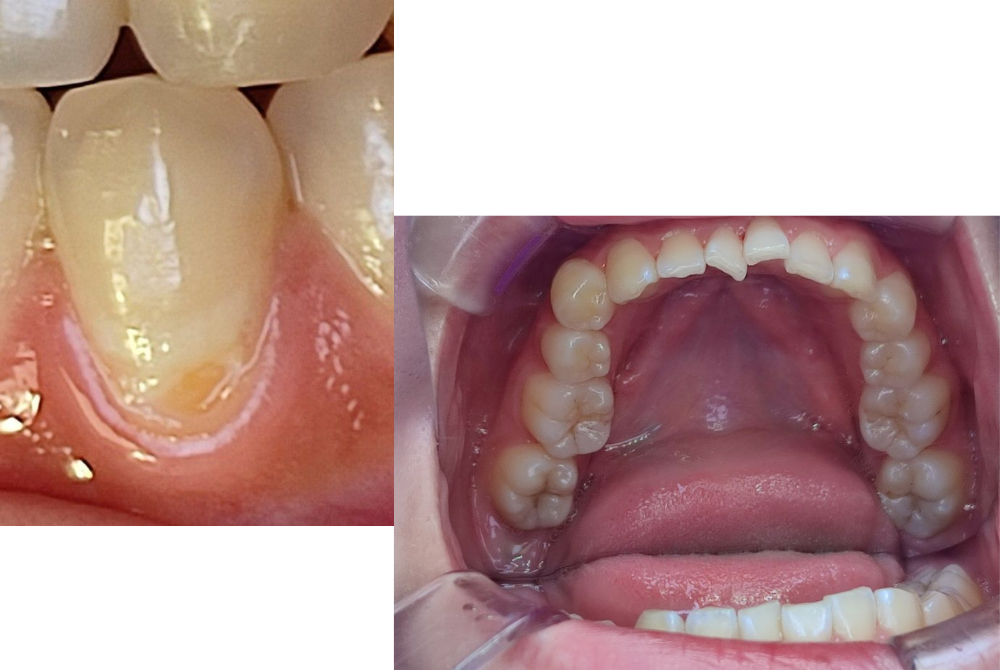

C1(初期の虫歯)

歯の表面(エナメル質)に小さな穴や白濁が現れる状態で、痛みはほとんどありません。

この段階であれば、削らずにフッ素塗布や経過観察で済む場合もあります。